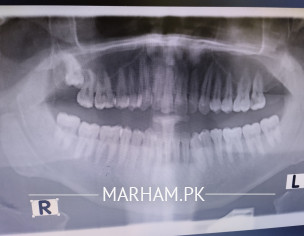

i am suffering from pain in my top left most tooth. sometimes i feel pain or sensitivity sometimes its perfect. but now from sometime its regular pain. my doctor has suggested for root canal. can i have second opinion. plus there is also a tooth of right top side that needs filling as well. can you people pls suggest me

pics not opening here .. after Opg full mouth x-ray take an appointment from marham to consult with us in lahore .... ur dental problem need immediate attention... no solution by text ... regards

The xrays donot show but do as your dentist has suggested